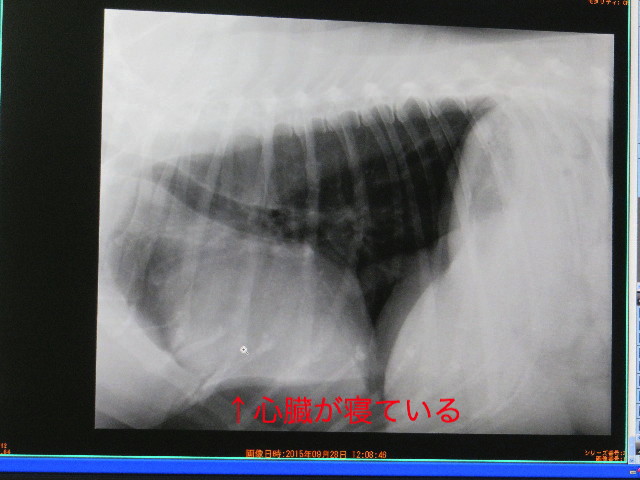

●右眼に眼底出血もありましたし、(腫瘍ができやすい)ゴールデンだし....ということで、久しぶりに【胸のレントゲン】を撮りましうということに。

結果は、特に大きな問題はありませんでしたが

もいちゃんの心臓の位置(というか形)は以前から“寝ていて”、右心室(だったかな?)が肥大気味とのこと。

以前撮ったレントゲンとほとんど変わっていませんが、言われてみれば確かに右が大きいです。

でも、胸部レントゲンでは、けっこう悪い所や腫瘍等はないので良かったです。(ホッ♪)